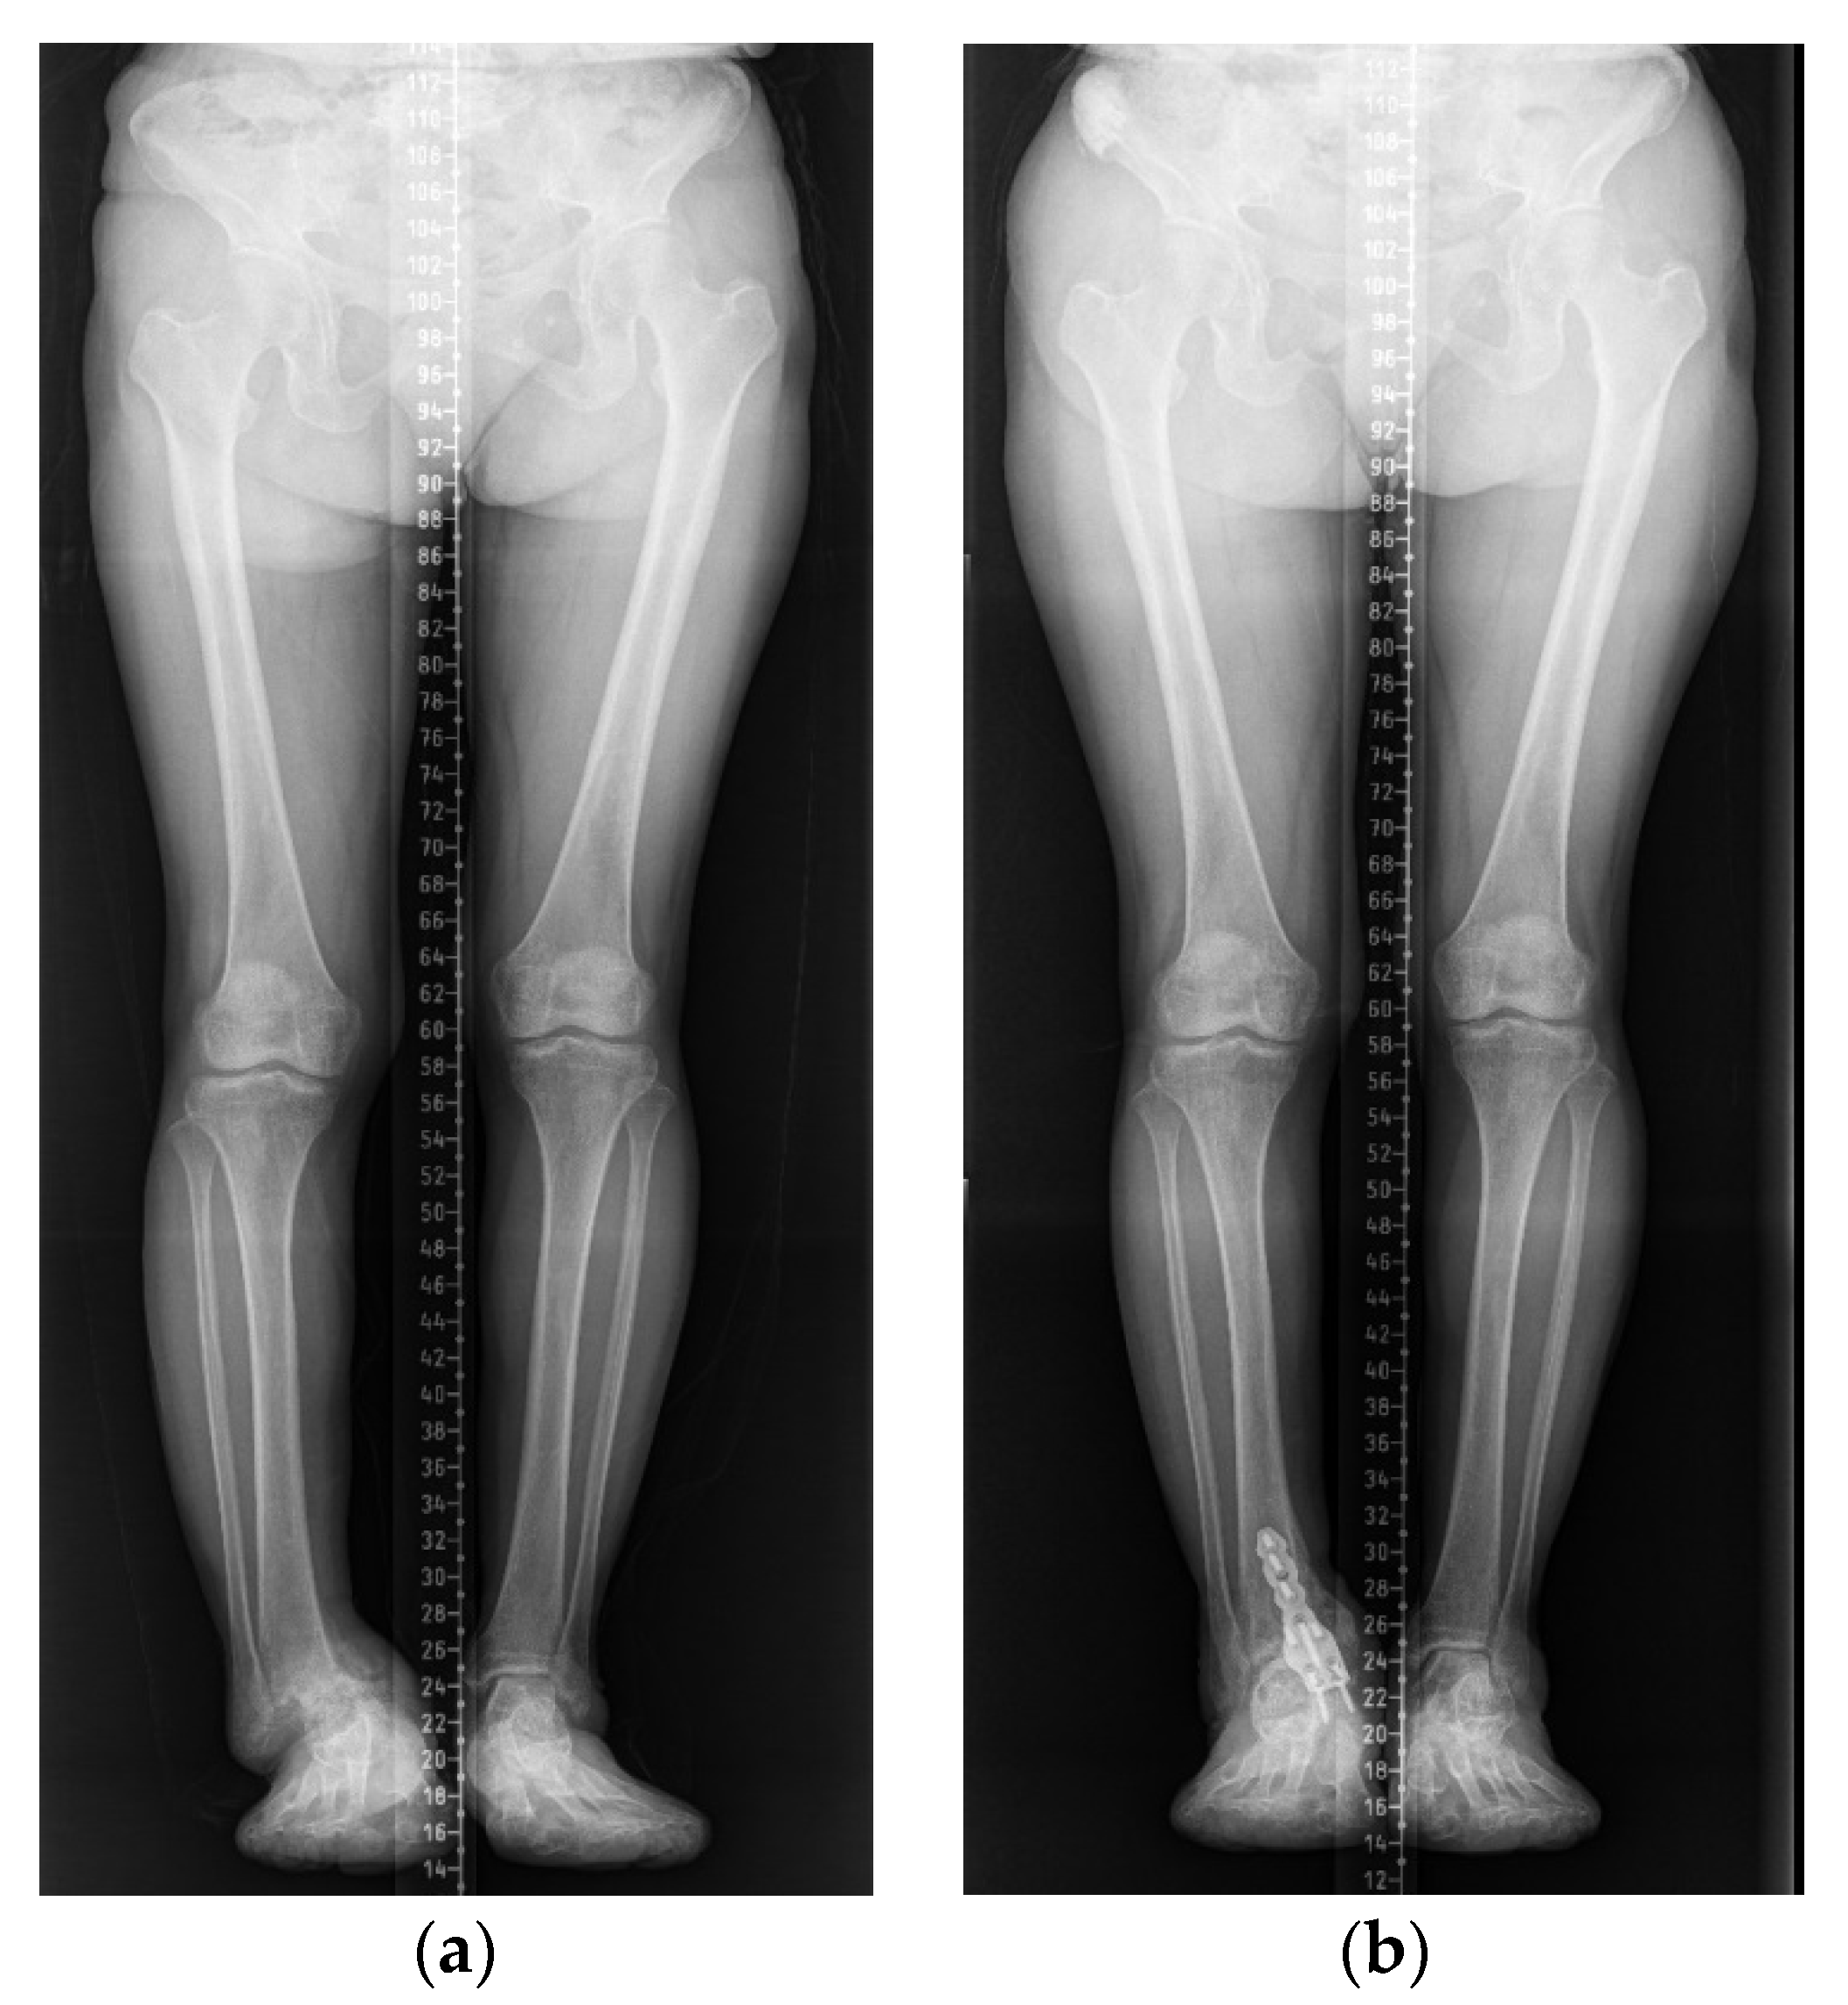

2. Case Presentation